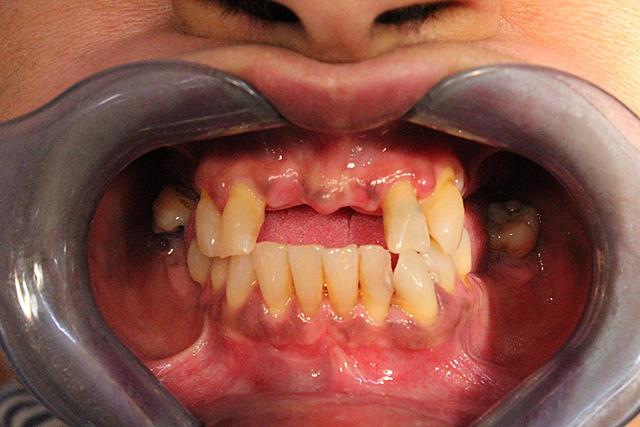

• Fotografías intraorales y extraorales

Fotografías intraorales y extraorales

Se tomaron las fotografías a la paciente para poder llevar una secuencia del antes y después